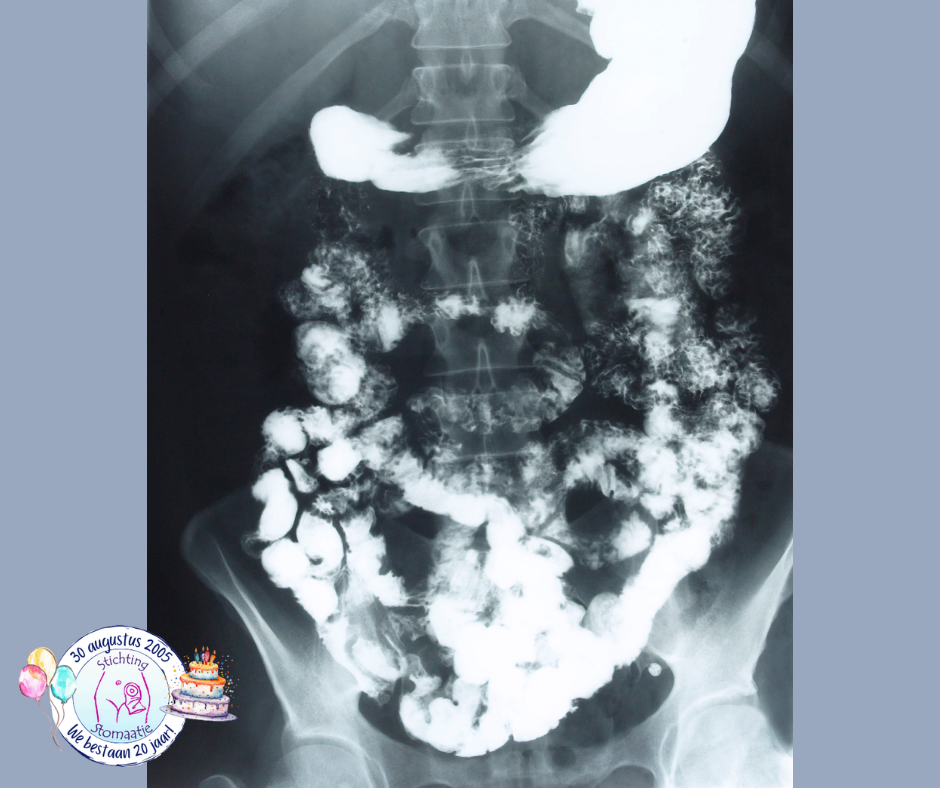

Buikoverzichtsfoto

Dit is een röntgenfoto van de gehele buik, waarbij geen contrastvloeistof (vloeistof die organen beter zichtbaar maakt op een röntgenfoto) gebruikt wordt. Bij ernstige verstopping is op de foto de stapeling van grote hoeveelheden ontlasting zichtbaar.

Pellet-passagetest

Een onderzoek waarbij ze de buikoverzichtsfoto gebruiken is de Pellet-passagetest. Je moet dan korreltjes of ringetjes slikken, die op een röntgenfoto zichtbaar zijn, zodat het transport van voedsel door het darmkanaal kan worden gevolgd. Daarna worden er een aantal dagen achter elkaar röntgenfoto's gemaakt, zodat te zien is waar de ringetjes zich in het darmkanaal bevinden. Zijn er bijvoorbeeld na 4 dagen nog steeds ringetjes zichtbaar dan is er sprake van verstopping. Aantallen markers en tijdschema verschillen per ziekenhuis.

Dit onderzoek wordt in het algemeen niet gedaan als er een verdenking is op een (ernstige) vernauwing of afsluiting van de darm, omdat de ringetjes dan kunnen vastlopen.